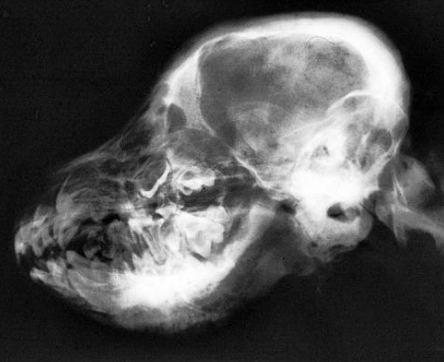

![]() | - mandible ์ชฝ ๊ฒฝ๊ณ๊ฐ ๋ฌด๋์ ธ ์์. - skull ๋ค์ชฝ์ด ํ์ฐํ ๋๊บผ์์ ธ ์์. |